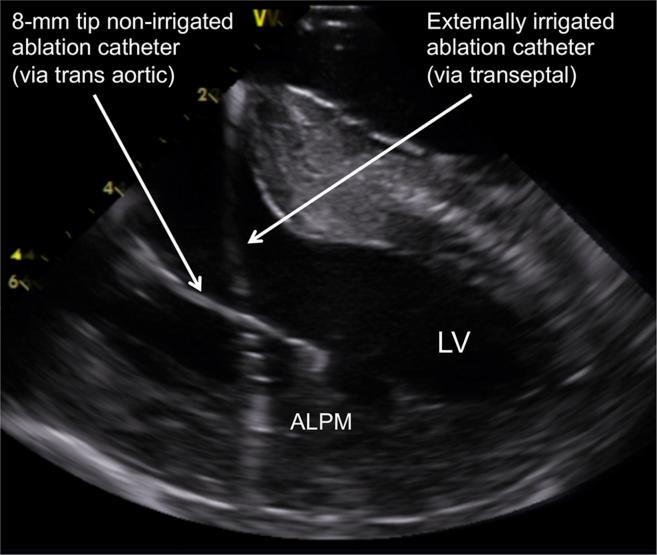

Successful bipolar radiofrequency catheter ablation of ventricular premature complexes arising from the anterolateral papillary muscle of the left ventricle.